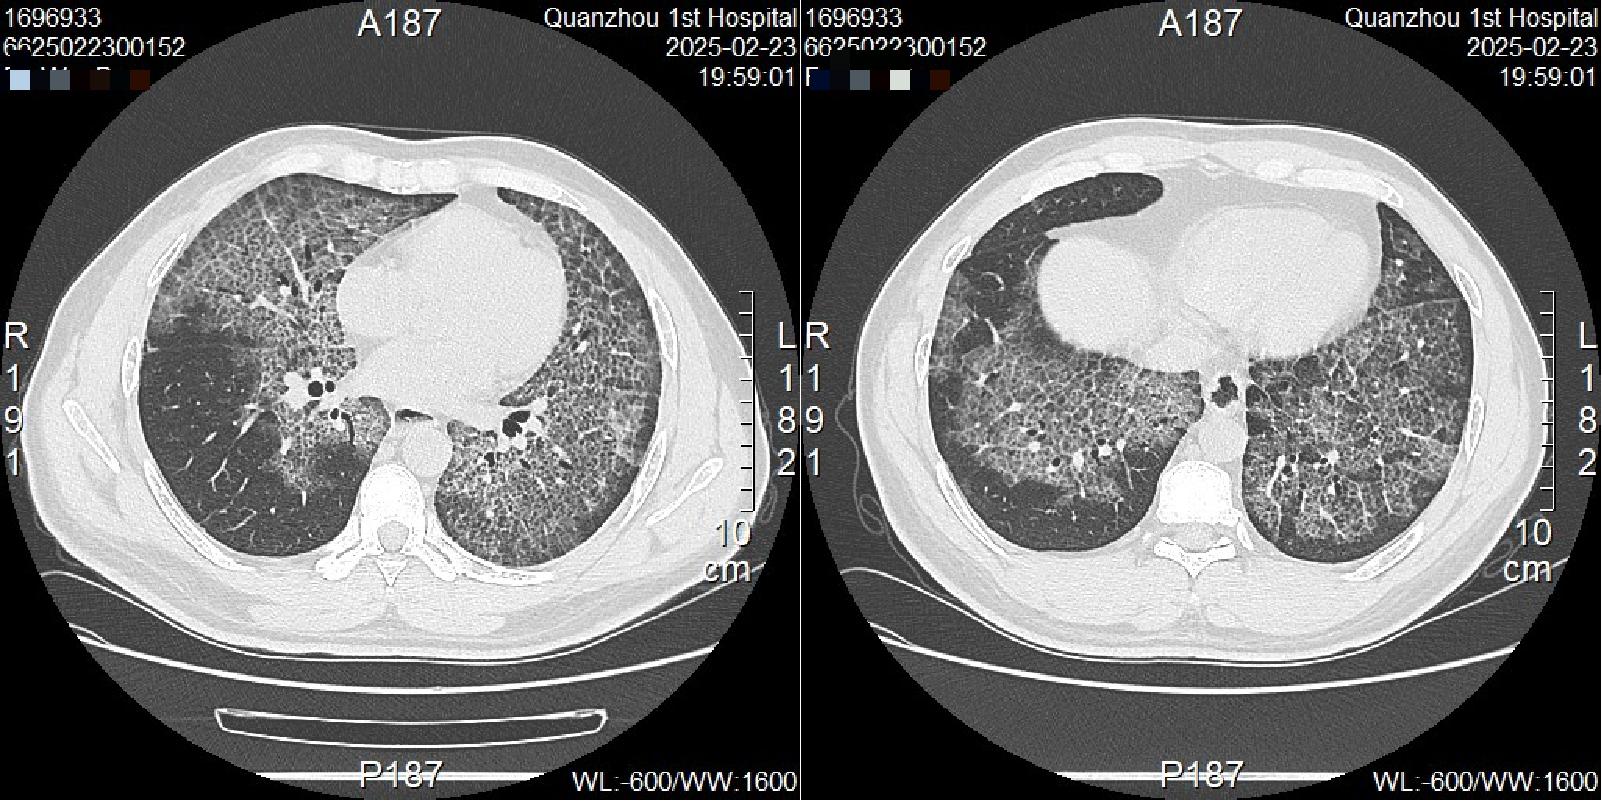

術前患者胸部CT顯示兩個大白肺

就診我院急診科行肺 CT 檢查時,發(fā)現(xiàn)肺部呈現(xiàn)彌漫白肺樣改變。經(jīng)呼吸與危重癥醫(yī)學科進一步通過支氣管鏡下肺泡灌洗及肺活檢病理、血GM-CSF抗體檢查等,傅先生最終確診為“自身免疫性肺泡蛋白沉積癥”。